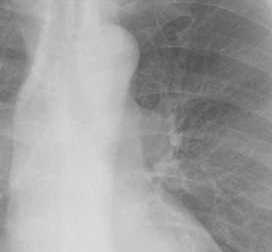

こちらを見て下さい。

わかりにくいかもしれませんが、このあたり。

気管が追いにくい、無くなっているようにも見えます。

気管狭窄ですね。こういう所見もレントゲンで捉えることができるのです。